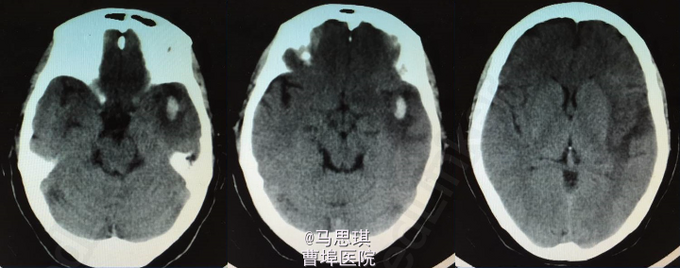

查体: PE:BP107/51 mmHg,双侧颈动脉未闻及杂音,双肺(—),心率80次/分,律齐,各瓣膜听诊区未闻及病理性杂音,腹(—),双下肢不肿。 NE:神清,部分性混合性失语,右侧轻度中枢性面舌瘫,右上下肢肌力Ⅴ-级,左上下肢肌力Ⅴ级,感觉对称、存在,腱反射++,病理征(—)。NIHSS评分:2分。 实验室检查:血常规示:WBC 14.3*10^9/L,中性粒细胞 80.8%,PCT 0.32 ng/ml。大小便常规、肝肾功能、电解质、血糖、风湿因子、ESR、血液流变学、HCY、血气分析、D-二聚体、心损、免疫全套、凝血、甲状腺功能、肿瘤标志物、腹部彩超、胸片正常,HIV(—),梅毒(—)。 TCho:4.45mmol/L ,HDL-C:1.31mmol/L ,LDL-C :2.41mmol/L ECG:窦性心律,ST改变。 UCG:左房稍增大,左室舒张功能稍减低。 TCD:椎-基底动脉血流速加快。 颈动脉彩超:双侧锁骨下动脉粥样斑块形成(软斑)。 入院头部CT:大脑镰旁多发钙化灶;脑实质未见明显异常改变。

入院诊断为:“脑梗塞?” 患者有溶栓指征,但患者家属拒绝溶栓。 治疗: 氯吡格雷75mg Qd 拜阿司匹林0.1 Qd 立普妥 20mg qd 胞磷胆碱0.2tid 依达拉奉30mg ivgtt bid 康复治疗 入院第二天行MRI及MRA检查。 头部MRI:左侧额颞岛叶见片状稍长T2稍长T1信号灶,其内见较多增粗、增多血管影,原因?考虑:血管畸形所致左侧额颞岛叶缺血梗塞性改变?血管炎性病变或脑炎待排? 头颅MRA:左侧额颞岛叶见较多增粗、增多的血管影,右侧额颞顶交界区血管影稍增多。左侧胚胎型大脑后动脉。 入院第四天行头颅增强CT及CTA。 头颅增强CT:左侧颞叶见片状低密度影,其内见大小约0.7x1.6cm片状高密度影,与前片比较,见范围加大,考虑系梗塞后伴出血,血管畸形。增强扫描见左侧额颞叶较多迂曲扩张的血管影。 CTA:左侧额颞岛叶区域见大脑中动脉岛叶段,侧裂段及分叉段分支明显增多,部分迂曲、扩张,呈杂乱走行的血管团样改变,考虑血管畸形可能;右侧额顶交界区血管影稍增多。双侧颈内和基底动脉及大脑前中后动脉显示清晰,其大小、走行、信号未见确切异常,各血管壁光整,管腔未见确切狭窄,走行自然。 发现出血后,停用双联抗小板治疗,并加做DSA DSA示:左侧颈外动脉分支脑膜中动脉血管畸形,与颈内动脉,椎动脉无明显交通 修正诊断为: 左侧额颞岛叶脑梗塞并梗塞后出血; 左侧脑膜中动脉血管畸形 动脉粥样硬化症 上呼吸道感染